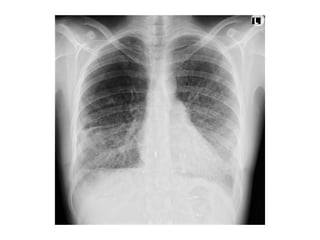

Centrilobular Emphysema